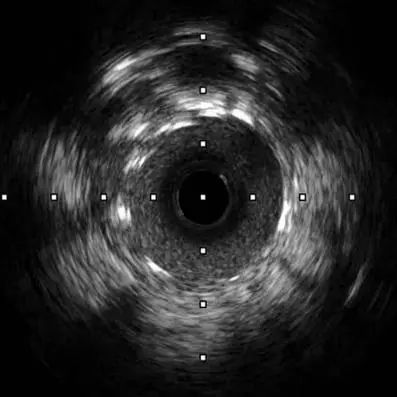

在6F EBU 3.5指引导管到位左冠后,沿前降支导丝送血管内超声(IVUS)导管无法通过病变,遂先予Sprinter 2.5×15mm球囊8atm扩张前降支病变,造影可见球囊膨胀呈“狗骨头现象”。球扩后再次送IVUS导管成功通过病变检查提示:病变处弥漫性纤维钙化斑块,局部可见180-330°钙化环,钙化厚度约0.2mm-0.4mm,长度约8mm,局部可见钙化小结。

复查IVUS清晰可见病变处环形钙化多处断裂,局部未见明显夹层,获得较大管腔,已满足支架植入条件。遂于左前降支近段成功植入3.0×18mm、3.5×15mm药物洗脱支架2枚。复查造影及IVUS提示支架膨胀良好,未见夹层及边支丢失,手术取得圆满成功。

图3.冲击波球囊处理前后的IVUS对比图像